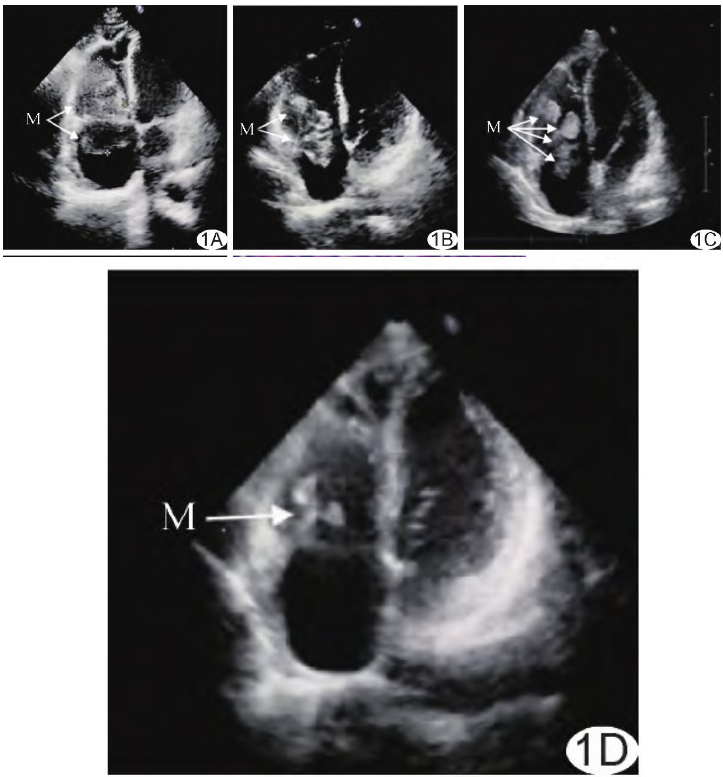

实验室检查:淋巴细胞计数0.68×109/L,血红蛋白109 g/L,血小板计数103×109/L,乳酸脱氢酶375.00 U/L,C反应蛋白20.17 mg/L。超声心动图:右心内82 mm×48 mm形态不规则中等偏低回声占位横跨三尖瓣(图1A),与右房室壁分界不清,活动度小;双侧股四头肌内低回声肿物,结合病史考虑为淋巴瘤转移。PET/CT:右侧胸膜及双肺内见结节,心脏肿瘤,多发肌肉占位,均伴代谢增高;考虑淋巴瘤多部位浸润。

最终临床诊断:胃DLBCL全身转移。化疗1周后超声示右心肿瘤缩小至71 mm×36 mm(图1B),双大腿肿块缩小;4周后右心肿瘤缩小至22 mm×17 mm, 呈高回声,三尖瓣启闭恢复正常(图1C),双大腿肿块消失;11周后右心高回声缩小至7 mm×7 mm(图1D)。本例报道经医院伦理委员会免除伦理审查。

图1 转移性右心DLBCL超声心动图。A.入院后;B.化疗1周后;C.化疗4周后;D.化疗11周后(M:肿物)